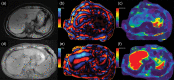

MRI is widely used in clinical practice for detecting liver diseases. Since the introduction of gadoxetic acid, MRI has become the most effective modality for the detection and characterization of focal liver lesions. According to previous meta-analyses, the area under the receiver operating characteristic curve (AUROC) was 0.97-0.99 for the diagnosis of small hepatocellular carcinoma (≥ 2 cm) by gadoxetic-acid-enhanced MRI. Moreover, the AUROC for the diagnosis of colorectal liver metastases was significantly high (0.98). Despite gadoxetic acid's drawbacks, its clinical utility outweighs them, making it the contrast agent of choice in routine liver MRIs. Moreover, clinically, liver MRI has become more prevalent for a quantitative assessment. Liver fibrosis can be evaluated using MR elastography; whereas, hepatic steatosis and iron overload can be evaluated using proton density fat fraction, with high accuracy and reproducibility. This article reviewed the usefulness of liver MRI, which can be a comprehensive imaging modality in clinical practice.